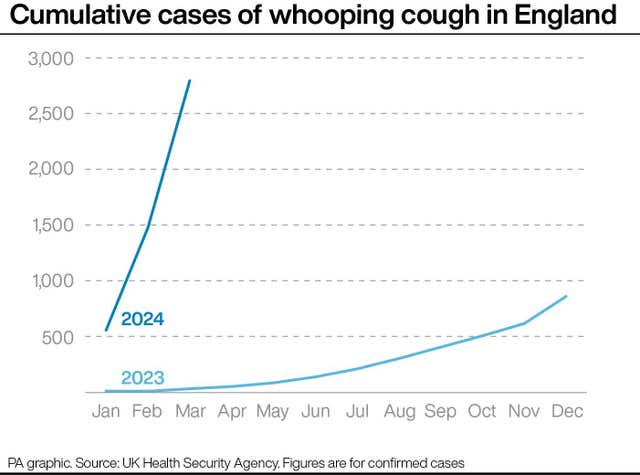

More than 2,700 whooping cough cases have been reported across England so far in 2024 – more than three times the number recorded in the whole of last year.

The UK Health Security Agency (UKHSA) figures show there were 2,793 cases reported to the end of March.

That compares to 858 cases for the whole of 2023.